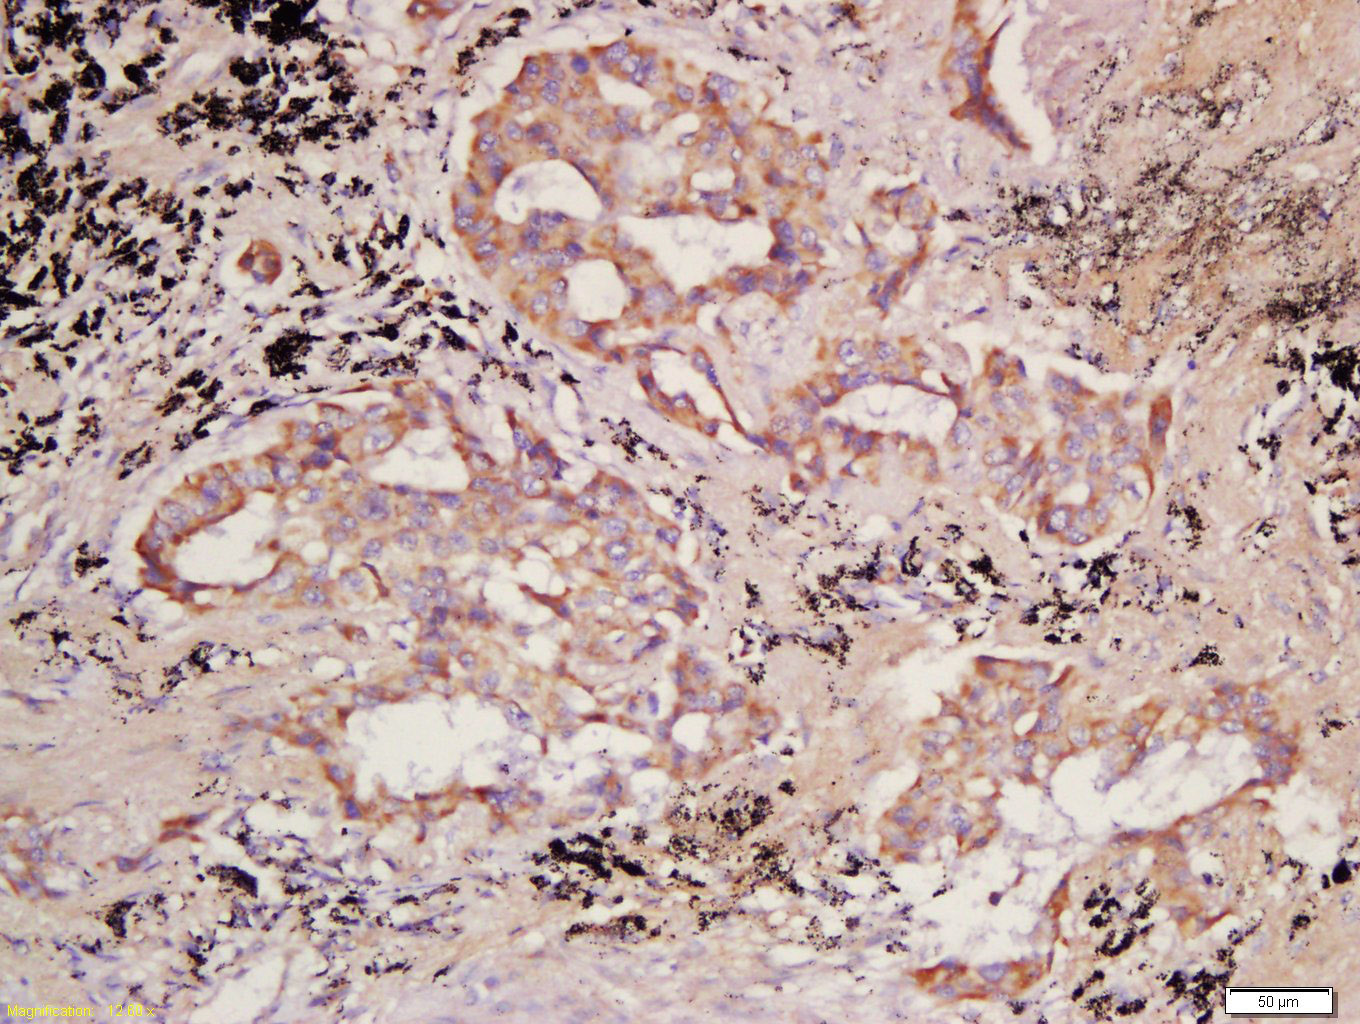

Tissue/cell: human lung carcinoma; 4% Paraformaldehyde-fixed and paraffin-embedded; Antigen retrieval: citrate buffer ( 0.01M, pH 6.0 ), Boiling bathing for 15min; Block endogenous peroxidase by 3% Hydrogen peroxide for 30min; Blocking buffer (normal goat serum,C-0005) at 37℃ for 20 min; Incubation: Anti-PCDHB10 Polyclonal Antibody, Unconjugated(bs-13725R) 1:200, overnight at 4°C, followed by conjugation to the secondary antibody(SP-0023) and DAB(C-0010) staining